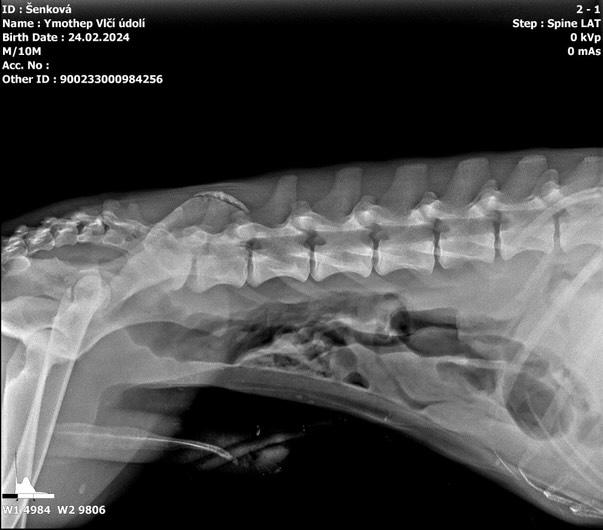

DOB: 02/24/24